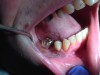

SDF is an antimicrobial liquid and desensitizing agent used to treat dentin hypersensitivity. It is available in the United States as a 38% solution. Like other desensitizing agents being used off-label as best practice for preventing incident dental caries, SDF offers the additional promise of arresting extant dental caries.18-20 SDF accomplishes this by being bactericidal and forming an acid-resistant protective layer on the tooth. The silver in SDF kills the cariogenic biofilm bacteria, and the fluoride inhibits demineralization and promotes remineralization of the dental hard tissue by converting hydroxyapatite to fluorapatite.19,20 As a result of applying SDF to a tooth surface, black staining precipitates as silver salts (silver phosphate), which become embedded in the active decay lesion, adjacent biofilm, and/or soft tissue. This light-sensitive compound will react to turn the decay from soft and brown to hard and black, and it may then be restored definitively as needed. The staining effect on the biofilm and soft tissue is transient and may be polished away or allowed to naturally desquamate (Figure 13 through Figure 15). Healthy tooth structure will remain unchanged and will not stain black.

Fig 13. Smooth-surface caries in a methamphetamine-using patient.

Figure 13

Fig 14. Appearance of lesions after one application of SDF.

Figure 14

Fig 15. Carious lesions restored with composite resin. Note satisfactory masking of dark staining after SDF treatment.

Figure 15